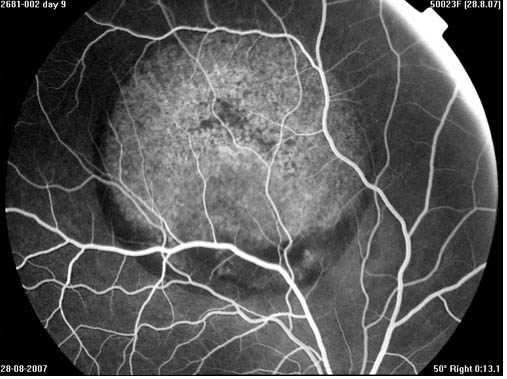

- Quantitative drug uptake, penetration, delivery and half life time studies in vivo in vitreous and retina.

- Quantitative drug uptake, penetration, delivery and half life time studies in vivo in vitreous and retina.

- Disease models

- Photoreceptor toxicity assessment